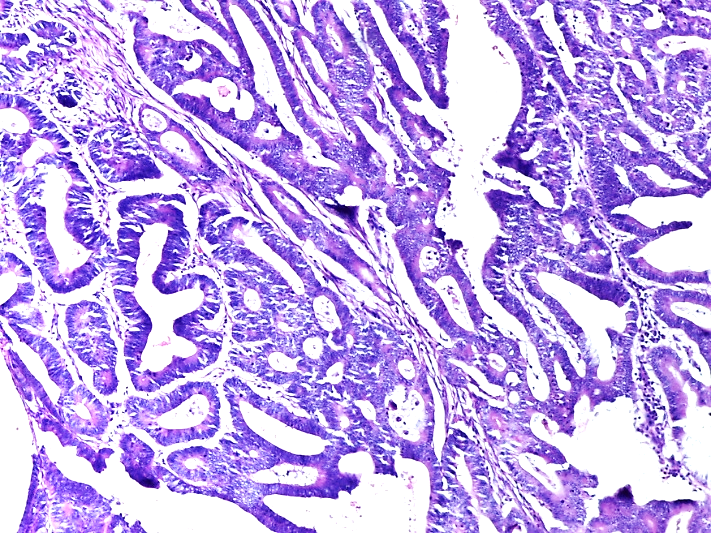

P53 expression in colorectal carcinomas study at a tertiary health care center in South Kerala

Alina Ajoy Thomas, Meeta Thomas, Jessy M.M

A histopathological study on breast carcinoma with special reference to cyclin-D1 and estrogen receptor

Payel Hazari , Monoj Kumar Deka, Bandana Kanoo